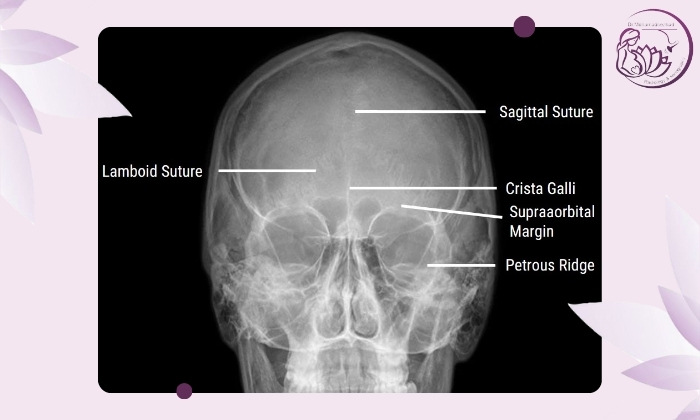

عکسبرداری معمولاً در حالتهای مشخص انجام میشود تا بتوان بهترین دید را به سینوسهای مختلف گرفت. سه نمای اصلی آن عبارتاند از:

نمای واترز (Waters View): برای بررسی سینوسهای ماگزیلاری (زیر چشم).

نمای کالدول (Caldwell View): برای مشاهده سینوسهای فرونتال و اتموئید (پیشانی و بین چشمها).

نمای لترال (Lateral View): نمایش سینوسهای اسفنوئید (پشت چشمها).

در این عکس اگر سینوسها شفاف و پر از هوا باشند به رنگ تیره دیده میشوند؛

اما اگر مایع یا التهاب وجود داشته باشد به رنگ روشنتر یا خاکستری دیده میشود.